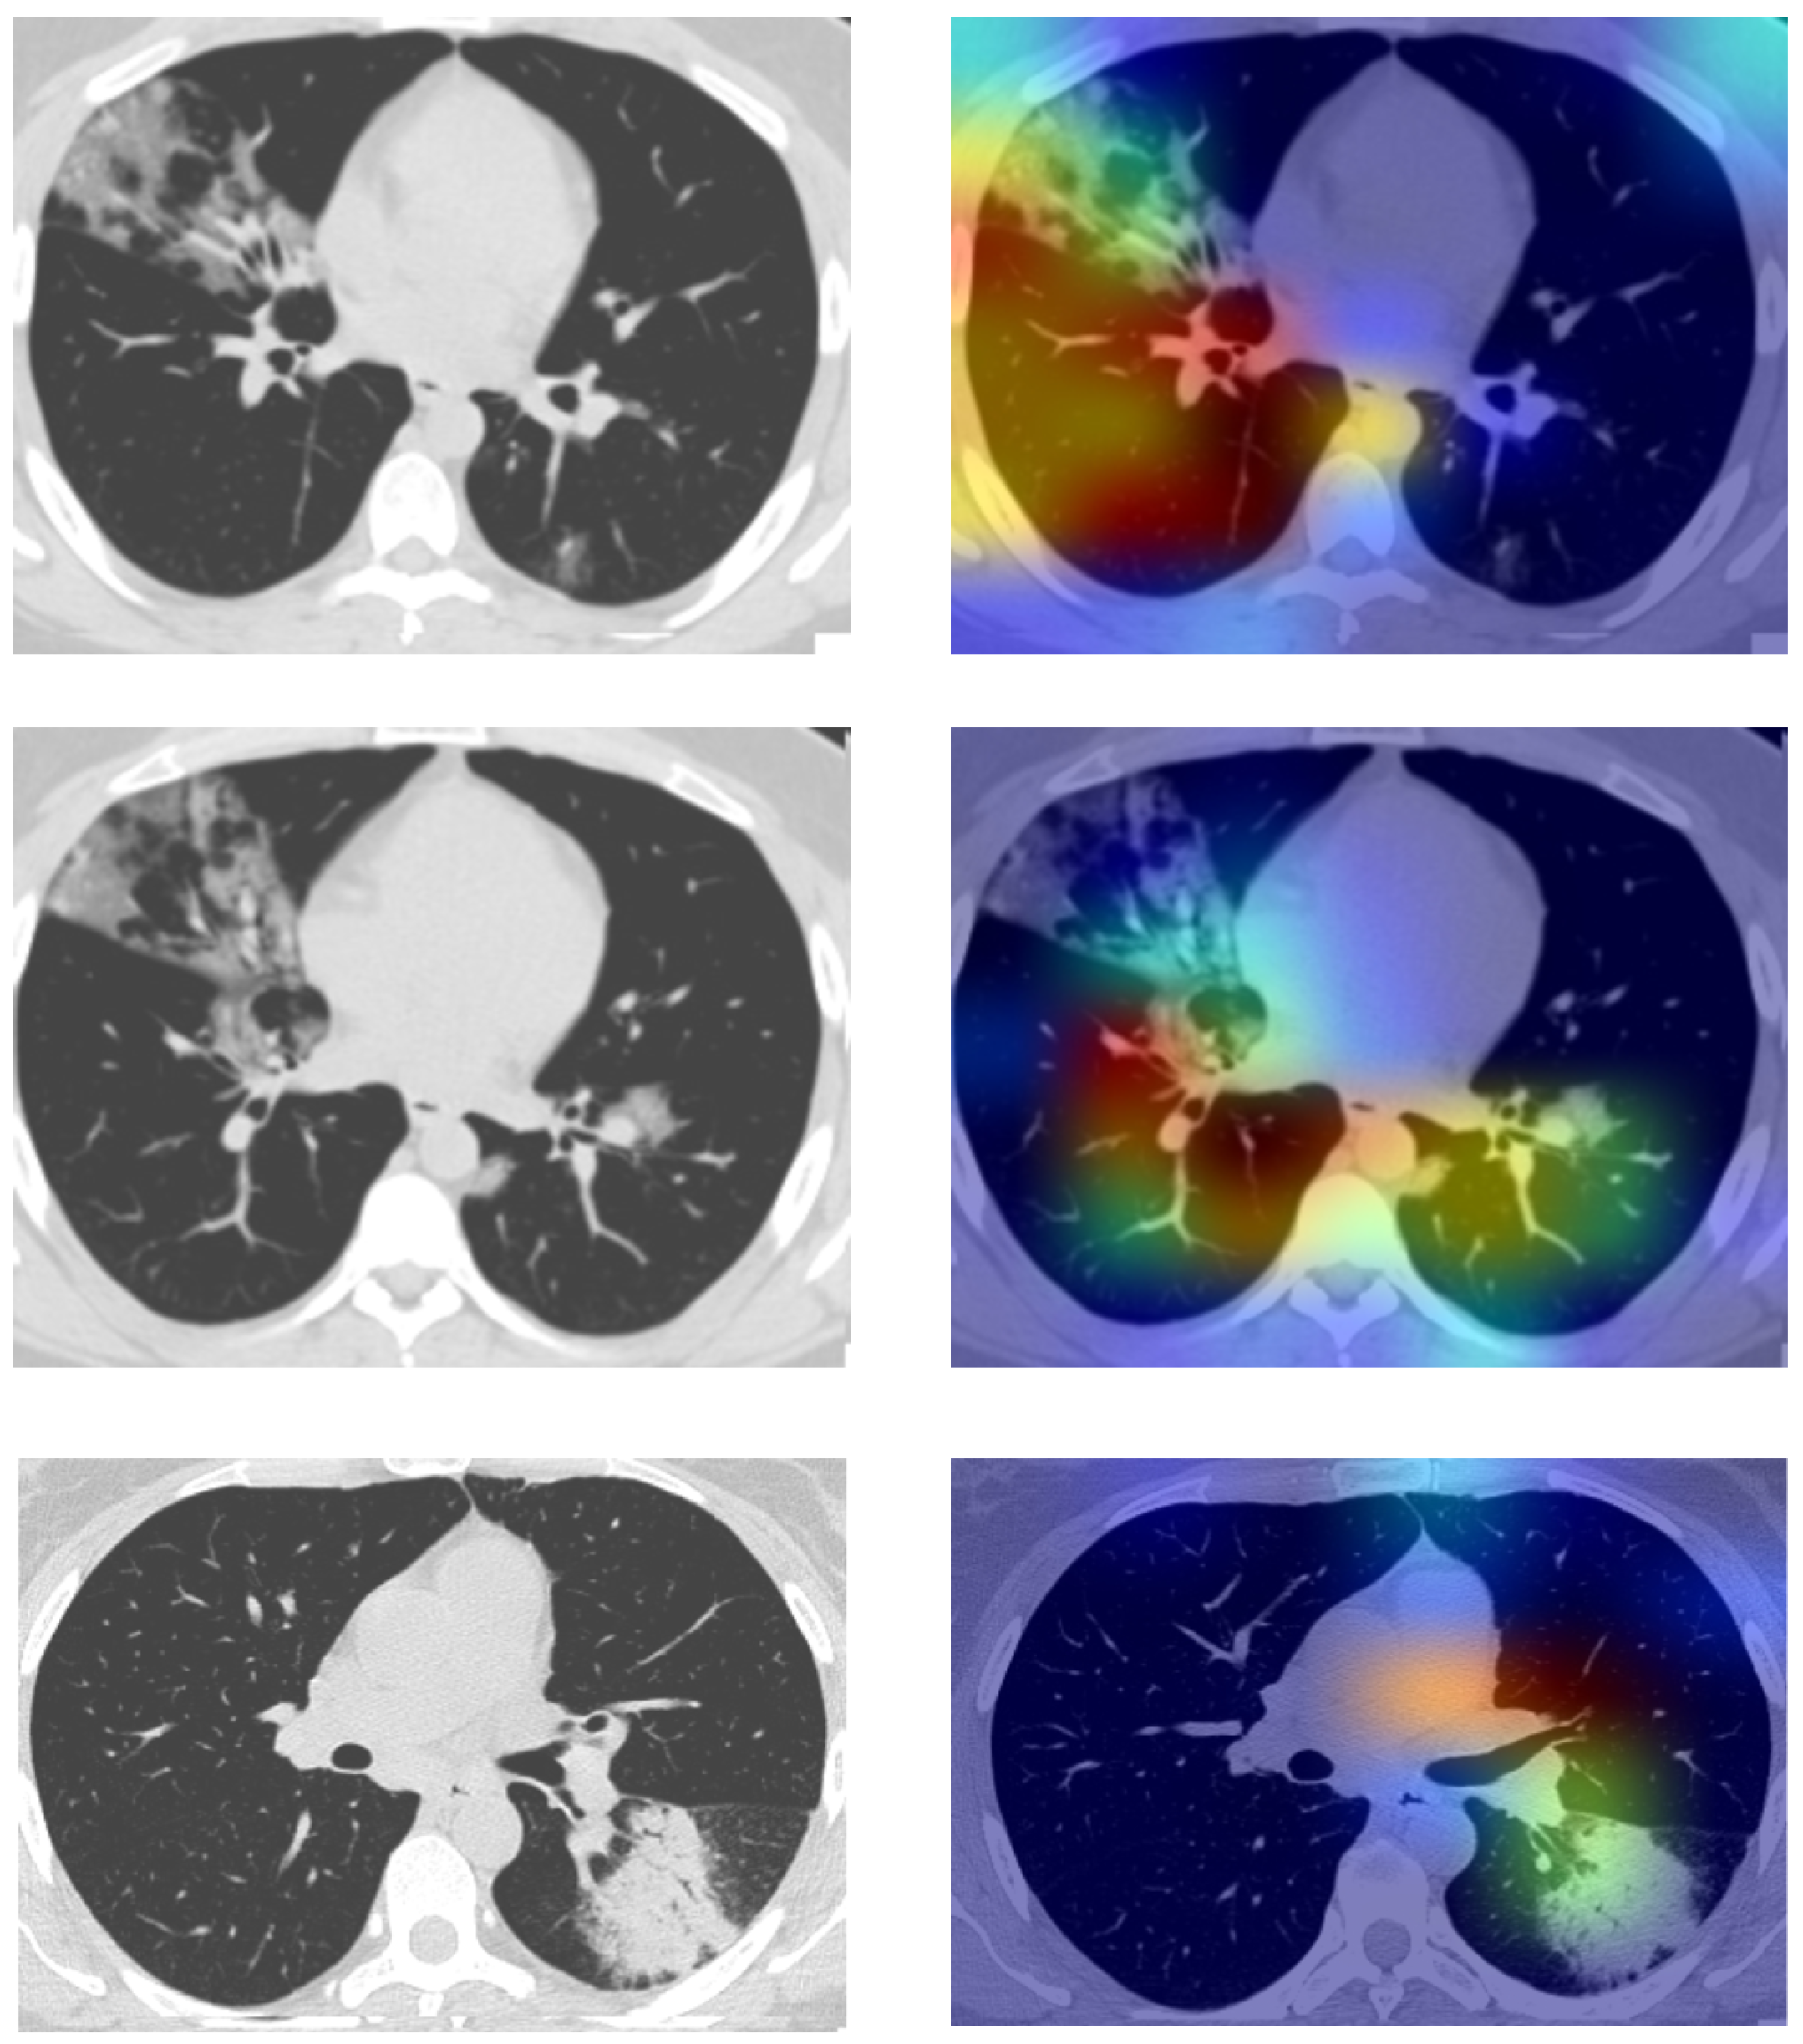

When the use case of a computer-aided framework is so sensitive, visual inspection is truly required. To create such visualizations, Grad-CaMS [60] or gradient-weighted class activation mapping can be utilized. It uses the gradients of any target concept flowing into the final convolutional layer to produce a coarse localization map, highlighting the important regions in the image for predicting the concept. To obtain the class discriminative localization map of width u and height v for any class c, at first, the gradient of the score for the class c is computed. These gradients flowing back are global average-pooled to obtain the neurons’ importance weights for the target class. After calculating the importance for the target class c, a weighted combination of activation maps is performed followed by ReLU activation. This results in a coarse heatmap of the same size as that of the convolutional feature maps. ReLU is applied to see the positive gradient have influence on the class of interest. As mentioned earlier, three DL-based models are used as base learners in this study. We tried to generate the Grad-CaM images to highlight the most important areas of an image, which influence the prediction made by the base learners. Figure 9 shows the produced Grad-cam images along with the original CT-scan images on the left.

Figure 9. Grad-CaM visualizations generated from the base learners highlighting the region of interest.